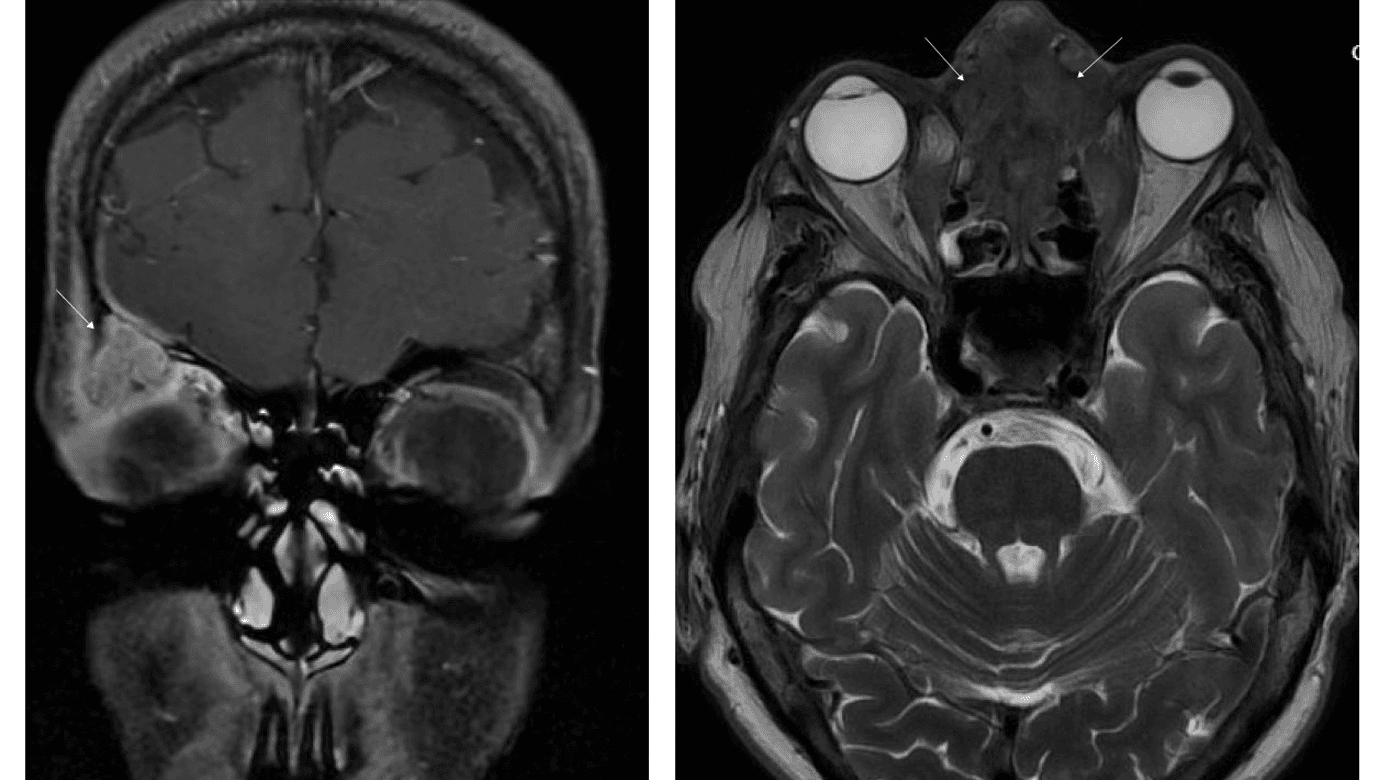

I. En otteårig, ellers sund og rask pige blev henvist til øjenafdelingen på grund af rødme og hævelse omkring det højre øje igennem en måned. Der var ingen næse-bihule-symptomer eller symptomer i øvrigt, og behandling med fusidin-creme eller phenoxymethylpenicillin havde ingen effekt. Objektivt fandtes rødme og hævelse omkring det højre øje, visus 1,0, normal tension, farvesyn, H-konfiguration, naturlig spaltelampeundersøgelse og oftalmoskopi. Patienten blev opstartet i amoxicillin/clavulansyre efter vægt på mistanke om præC. Grundet manglende fremgang efter endt kur blev der udredt med MR-skanning af orbita. Denne viste en 15 × 16 × 12 tumorsuspekt forandring superolateralt i orbita (Figur 1 A). Patienten blev henvist til Øjensygdomme, Aarhus Universitetshospital, og herfra videre til Neurokirurgisk Afdeling. På udredningstidspunktet på Neurokirurgisk Afdeling, hvor der var gået ca. tre uger, var hævelsen svundet helt. Ved gennemgangen af skanningen var der mistanke om, at forandringen kunne repræsentere et mucocele. Kontrol-MR-skanning tre måneder efter viste fuld regression af forandringen.

II. En 57-årig kvinde blev henvist til øjenafdelingen, obs venstresidig dacryocystitis. Patienten havde gennem en måned en voksende hævelse ved den øvre, mediale øjenkrog uden smerter eller feber. Hun blev opstartet i amoxicillin/clavulansyre, og grundet manglende fremgang på behandlingen og den atypiske placering ved den øvre del af næseryggen blev der henvist til MR-skanning af orbita. Skanningen viste udbredte tumorforandringer i sinus ethmoidales (Figur 1B), kranielle del af cavum nasi og medialt i begge orbita. Canceren havde udgangspunkt i etmoidalcellerne og var på stadie T4b, N1, M0. Patienten blev opstartet palliativt i højdosisstråleterapi og kemobehandling.